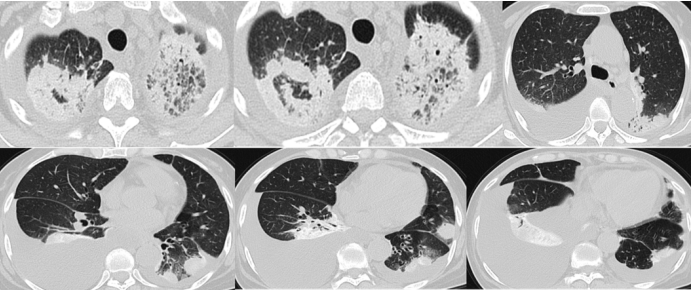

胸部CT:双肺多发中高密度炎性病灶,双上肺为著。部分肺组织受压不张,双侧胸腔积液;纵隔见多发肿大淋巴结;心脏增大,心包积液(图3

图片

图3  患者入院时胸部CT

拟诊:脓毒症,多脏器功能不全,肿瘤不除外。给予高流量呼吸支持,胸腔穿刺+持续闭式引流,抗感染,脏器保护+营养支持治疗,同时行BALF、胸水、外周血标本的传统病原学检查(涂片,培养,PCR,抗原,抗体)结果均阴性;外周血结缔组织病、血管炎相关疾病阴性;血及胸腔积液肿瘤标志物中仅CA125、CA199轻度升高;胸腔积液+BALF脱落细胞学阴性。